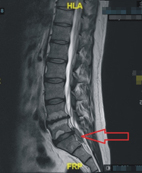

核磁共振的縱切面:可以看到明顯的椎間盤突出(箭頭處)往下游離 治療方式